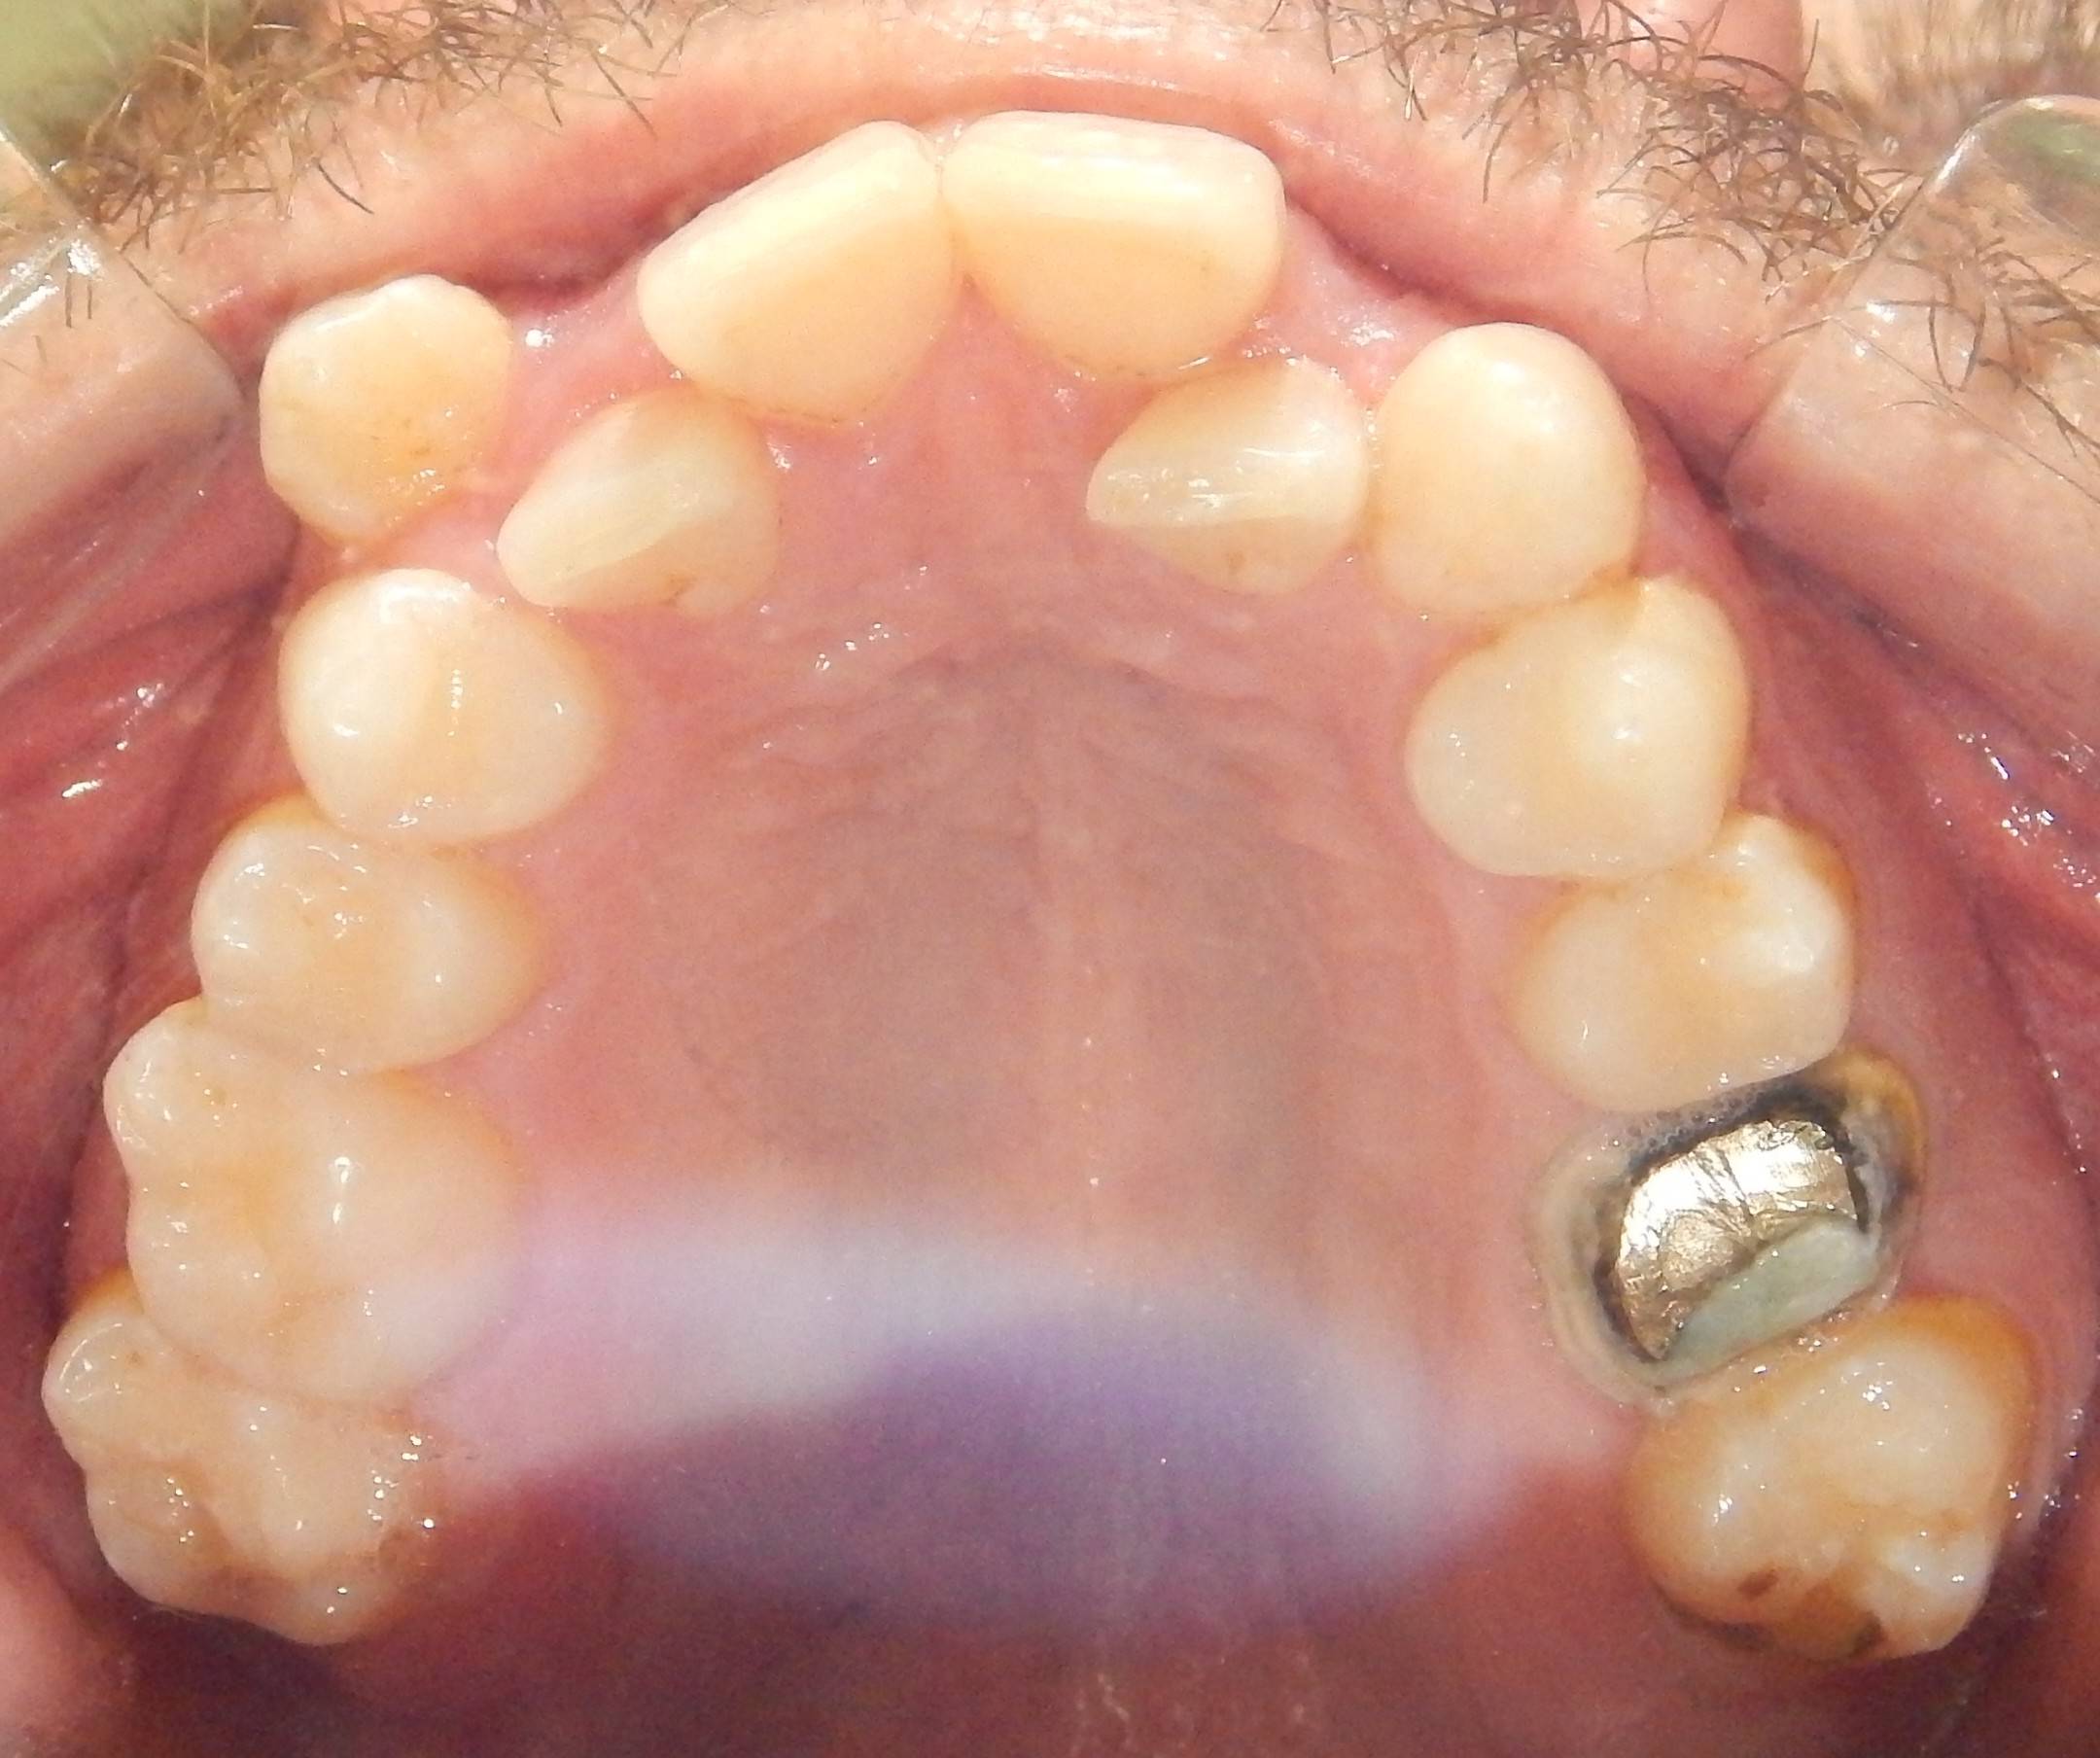

Implante y corona

Este paciente de 31 años acudió a la consulta porque había perdido una muela y deseaba rehabilitar su sonrisa. Nuestro cirujano colocó un implante dental en el espacio donde faltaba la pieza, y tras el tiempo necesario para que el implante se integrara correctamente al hueso, confeccionamos una corona en nuestro propio laboratorio. De esta manera, logramos devolverle tanto la función como la estética. El resultado fue tan natural que el paciente quedó encantado: la corona se mimetiza perfectamente con el resto de sus dientes, pasando completamente desapercibida.